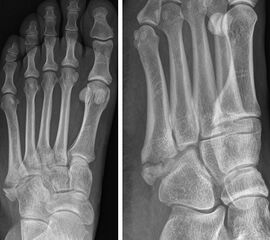

Lawrence und Botte Zone II

Abbildung 4

Kontrovers diskutiert wird die Behandlung der Frakturen in Zone II nach Lawrence und Botte (Abb. 4). Wie einleitend beschrieben, scheint hier unter anderem die inkonsistente Terminologie ursächlich zu sein. Das Synonym „Jones’ Fraktur“ oder „True Jones’ Fraktur“ wurde sowohl für Lawrence und Botte Zone II, als auch für Zone III Frakturen verwendet 1986. Entsprechend ist die Interpretation dieser Studien nur eingeschränkt möglich. 2013 publizierten Roche und Calder 20 eine systematische Literaturarbeit, in welcher sie die Ergebnisse verschiedener Behandlungsstrategien für „Jones Frakturen“ analysierten. 26 Studien mit 630 Frakturen (Level of Evidence I-IV) wurden eingeschlossen. 358 der Frakturen wurden operativ behandelt. Die knöcherne Konsolidierungsrate für operativ versorgte Frakturen betrug 96%, die für konservativ behandelte Frakturen 76%. Allerdings erfolgte keine Differenzierung zwischen Lawrence und Botte Zone II und Zone III Frakturen. Spezifischere Ergebnisse lieferte eine weitere systematische Literaturarbeit 7. In dieser wurden nur prospektive Studien eingeschlossen, in welchen die Frakturen nach Lawrence und Botte klassifiziert wurden bzw. klassifiziert werden konnten. Die Autoren kamen zu dem Ergebnis, dass die frühfunktionelle Behandlung von Lawrence und Botte Zone I und Zone II zu guten bis sehr guten Ergebnissen führt.